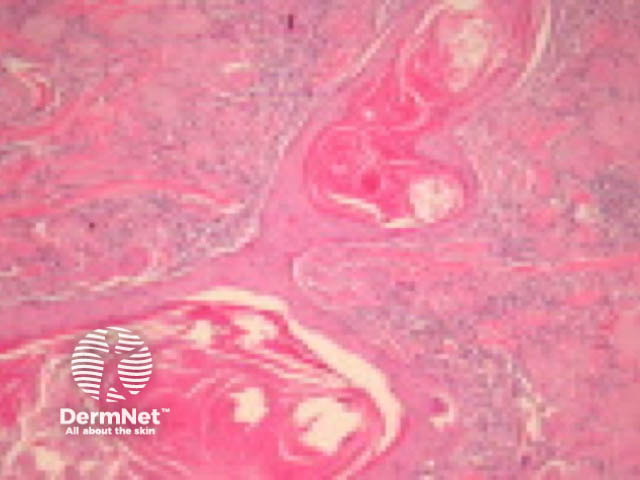

Typical SCC has nests of squamous epithelial cells arising from the epidermis and extending into the dermis (figure 1). The malignant cells are often large with abundant eosinophilic cytoplasm and a large, often vesicular, nucleus. Variable keratinisation (keratin pearls etc) is present (figure 2).

Figure 2